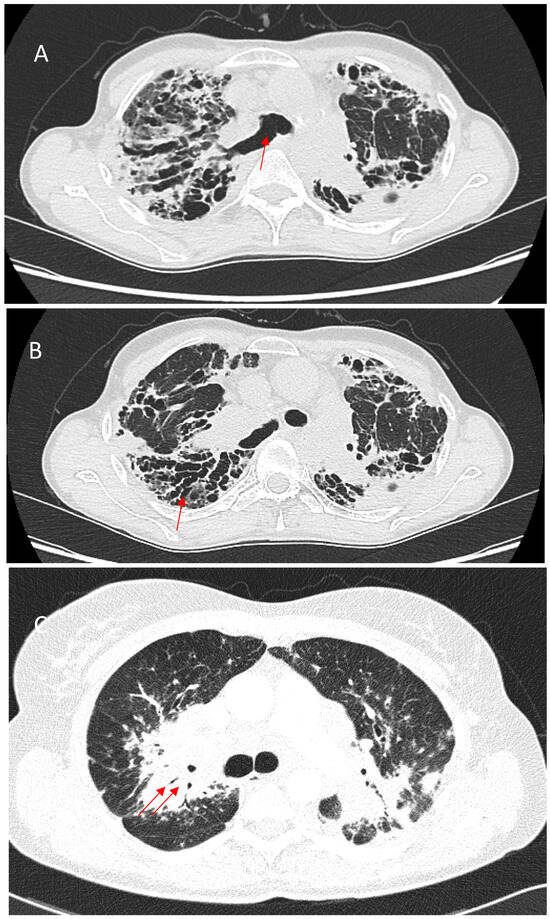

Background and Objectives: The pulmonary sequelae of COVID-19 and their evolution are of interest to the scientific community. We aimed to determine the radiological changes at 6 and 12 months after COVID-19 pneumonia, its evolution and its risk factors. Materials and Methods [...] Read more.

Background and Objectives: The pulmonary sequelae of COVID-19 and their evolution are of interest to the scientific community. We aimed to determine the radiological changes at 6 and 12 months after COVID-19 pneumonia, its evolution and its risk factors. Materials and Methods: This retrospective longitudinal study included adults admitted for COVID-19 pneumonia from 1 March 2020 to 30 April 2021 who had a high-resolution computed tomography (HRCT) scan at 6 months and 12 months after hospital discharge. The primary outcome was the appearance of radiological abnormalities on HRCT and the number of lung segments affected by them at 6 and 12 months, while the main explanatory variables were about the disease course, analytical parameters and treatment. Results: This study included n = 108 patients, with a mean age of 64 years. There was a decrease in the percentage of patients presenting parenchymal (93.5% to 88.9%, p < 0.001) and reticular (63% to 62%, p < 0.001) patterns on HRCT at 12 months compared to 6, and an increase in those presenting a fibrotic pattern (62% to 63.9%, p < 0.001). Ground-glass opacities were the most frequent radiological change at 6 and 12 months (91.7% and 87%, respectively). There was a significant reduction in the total number of lung segments with ground-glass opacities (445 to 382, p < 0.001) and consolidation (158 to 136, p = 0.019) and an increase in those with bronchiectasis (66 to 80, p = 0.033) between the two moments. After multivariate analysis, high-flow oxygen therapy (HFOT), highest ferritin levels, hypertension and ≥71 years showed an association with the development of subpleural parenchymal bands, consolidation, bronchiectasis and septal thickening at 6 and 12 months. Conclusions: Parenchymal patterns seem to be more frequent than reticular and fibrotic patterns after COVID-19 pneumonia. The fibrotic pattern was the only one that worsened significantly over time, with bronchiectasis being the only change that increased at 12 months. Older age, hypertension, the need for HFOT, and high levels of ferritin may be directly associated with worse radiological outcomes after COVID-19 pneumonia. Full article

Figure 1